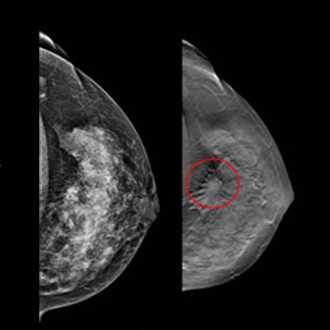

Mammography is important because in its earliest stages breast cancer may not be palpable; it may be too small to feel as a lump or tissue change. Mammography can help detect these changes two years or more before you would feel them. Physical examination is also important because premenopausal breast tissue is often dense and fibrous, which may decrease the reliability of mammography for young women.

If a lump is detected after the mammography is done, it may be essential to take a biopsy for the final diagnosis.

Breast screening (mammography) is an X-ray examination of the breasts Breast screening can show breast cancer at an early stage, when they are too small for you or your doctor to see or feel

Breast screening can help find small changes in the best it shows up. Early detection of breast cancer offers the best chance of successful treatment, which significantly improves a woman’s chance of survival.